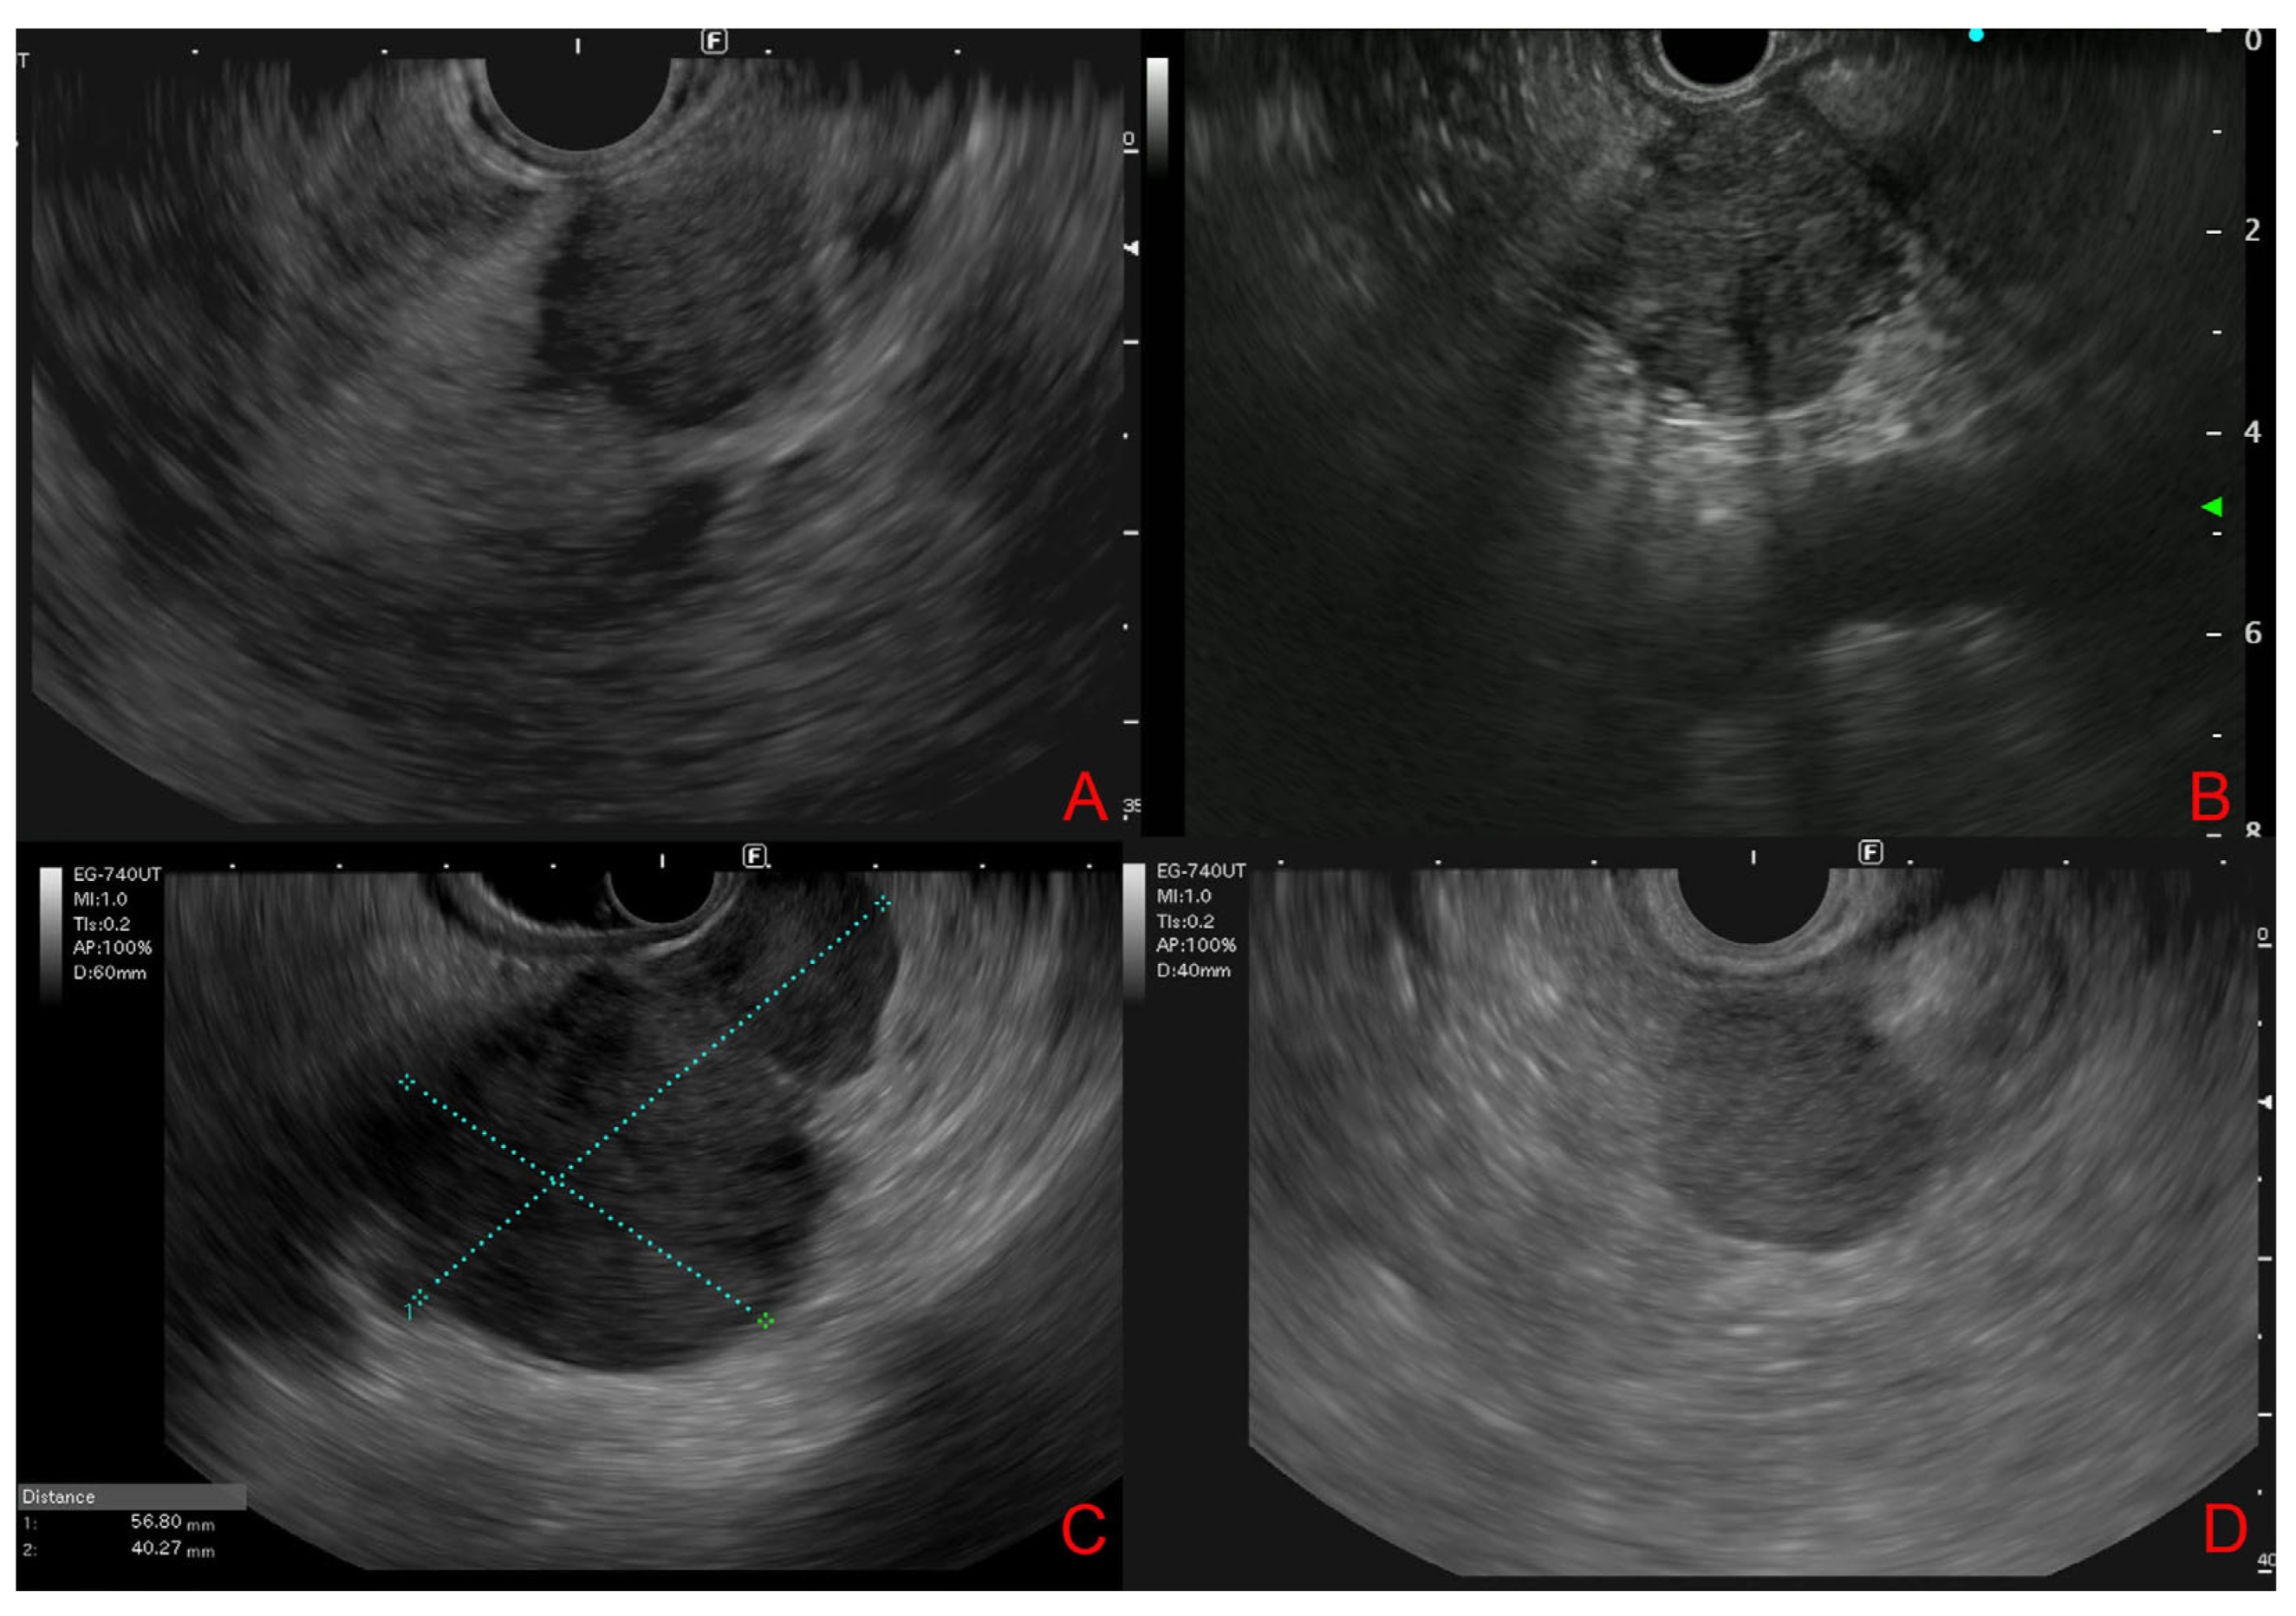

3.4. Endoscopic Ultrasound Morphological Features

| EUS morphology |

Round shape

Well-defined borders Typically hypoechoic with homo-/heterogeneous echotexture |

Ill-defined shape

Irregular borders Hypoechoic with heterogeneous echotexture Upstream main pancreatic duct dilation |

Well-defined borders Hypo-/isoechoic with homogeneous echotexture Hypervascular Hypoechoic rim |

Nodular shape

Irregular borders Hypoechoic with heterogeneous echotexture |